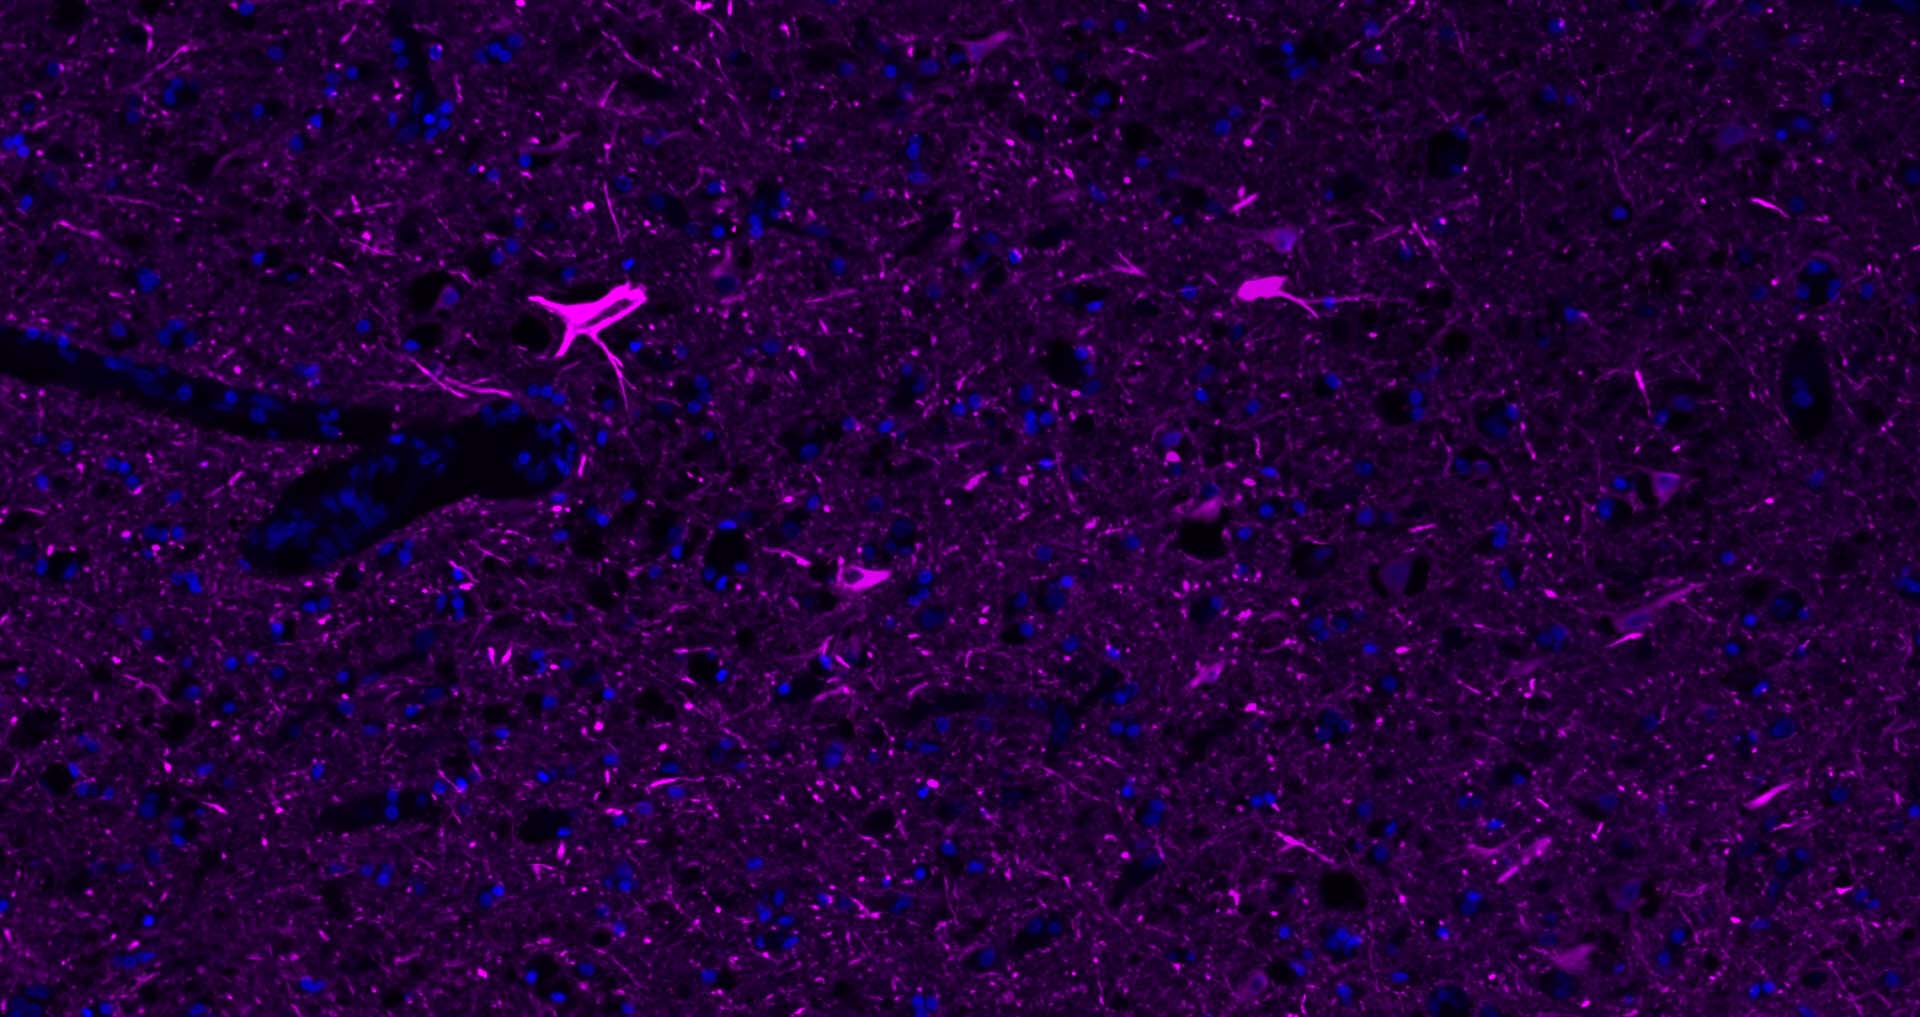

Paraformaldehyde-fixed, paraffin embedded Mouse Cerebrum; Antigen retrieval by boiling in sodium citrate buffer (pH6.0) for 15 min; Antibody incubation with NF-L Polyclonal Antibody, Unconjugated (bs-0707R) at 1:200 overnight at 4°C. Followed by conjugated Goat Anti-Rabbit IgG antibody (Purple, bs-0295D-Cy5), DAPI (blue, C02-04002) was used to stain the cell nuclei.

Paraformaldehyde-fixed, paraffin embedded Rat Cerebrum; Antigen retrieval by boiling in sodium citrate buffer (pH6.0) for 15 min; Antibody incubation with NF-L Polyclonal Antibody, Unconjugated (bs-0707R) at 1:200 overnight at 4°C. Followed by conjugated Goat Anti-Rabbit IgG antibody (Purple, bs-0295D-Cy5), DAPI (blue, C02-04002) was used to stain the cell nuclei.